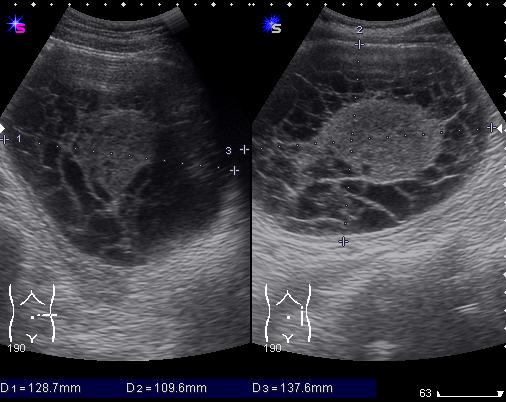

М. 37 лет, жалоб нет, амб. приём, причина назначения УЗИ ОБП: СОЭ 42мм

б\б и м\э консист., как говорится.   Исходит из н\ полюса левой почки

Очень необычное для почки образование. Первая мысль - RCC.

Коллега,очень хотелось бы посмотреть"исход" из н/полюса,хотя бы один снимок(из почки?пери или паранефрално?)Очень интересное "явление".Может быть и нагноившийся паразит?